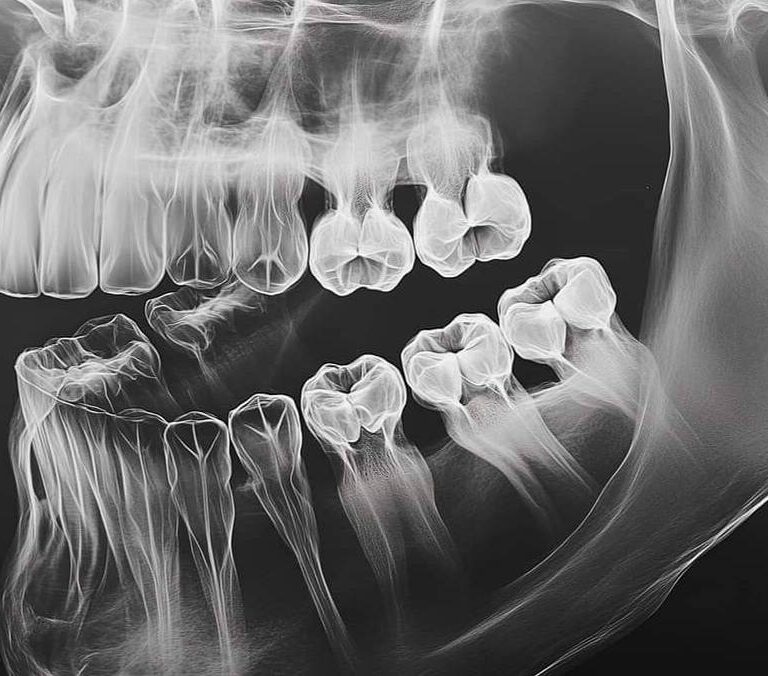

Necessity of a Microscope in Dentistry at DentalClinic24 – How Magnification and Visual Control Improve Treatment Precision

Precision in dentistry is determined not only by the clinician’s experience, but also by the level of visual control over the working field during treatment. Within the clinical approach of